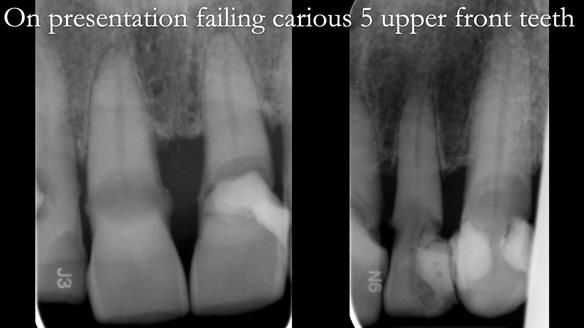

Natural 5 upper anterior teeth with caries and periodontal disease. Not restorable predictably.

The detailed clinical situation and treatment process are outlined below, with clinical work provided by me and technical work by Rowan Garstang. The treatment spanned 12 months, involving removing 5 upper anterior teeth, adding to an existing upper RPD, followed by creating and fitting metal based complete dentures.